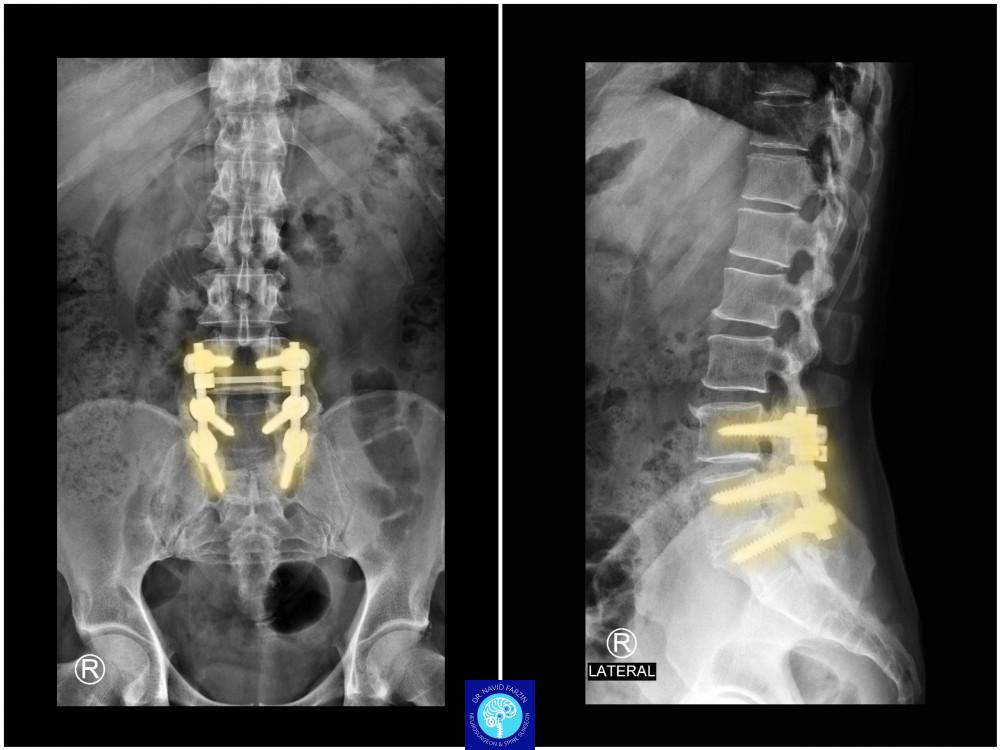

جراحی ستون فقرات

مدیریت شکستگی‌های ناشی از ضربه یا پوکی استخوان با روش‌های غیرتهاجمی و جراحی، برای پیشگیری از درد و محدودیت حرکت.

جراحی شکستگی و پوکی مهره‌ها

مدیریت شکستگی‌های ناشی از ضربه یا پوکی استخوان با روش‌های غیرتهاجمی و جراحی، برای پیشگیری از درد و محدودیت حرکتی.